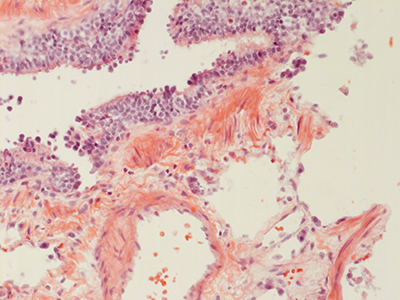

31 Year Old Adult Human Lung DD034L H&E